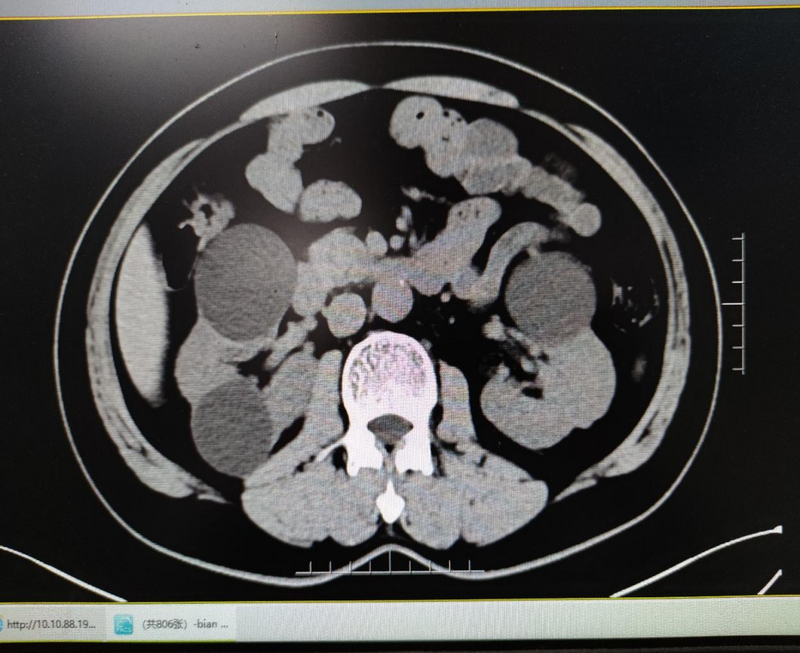

家住雨山的卞先生,現年53歲,因“檢查發(fā)現雙腎囊腫6年”在外院就診,CT檢查提示雙腎多發(fā)囊腫,左腎較大者4.8cm*4.7cm,右腎較大者為5.3c*5.2cm?;颊邥r有雙側腰部脹痛不適癥狀,外院醫(yī)生建議行后腹腔鏡下右腎囊腫去頂減壓手術治療,三月后再次行左腎囊腫手術?;颊弑救藶榘毯垠w質,加上對分期手術心存顧慮,想通過微創(chuàng)方式一次性同時解決雙側腎囊腫,但經過網上咨詢得到的絕大多數答復均需要行分期手術?;颊呶迥昵霸谖以盒小案文夷[去頂減壓手術”,秉承著對醫(yī)院的信任,再次來到醫(yī)院的泌尿外科就診。泌尿外科王龍信副主任接診后經仔細閱片,患者存在雙側腎臟多發(fā)囊腫,但囊腫大多位于腹側,存在行經腹單孔腹腔鏡手術同時處理雙側腎囊腫可能,遂收住入院。